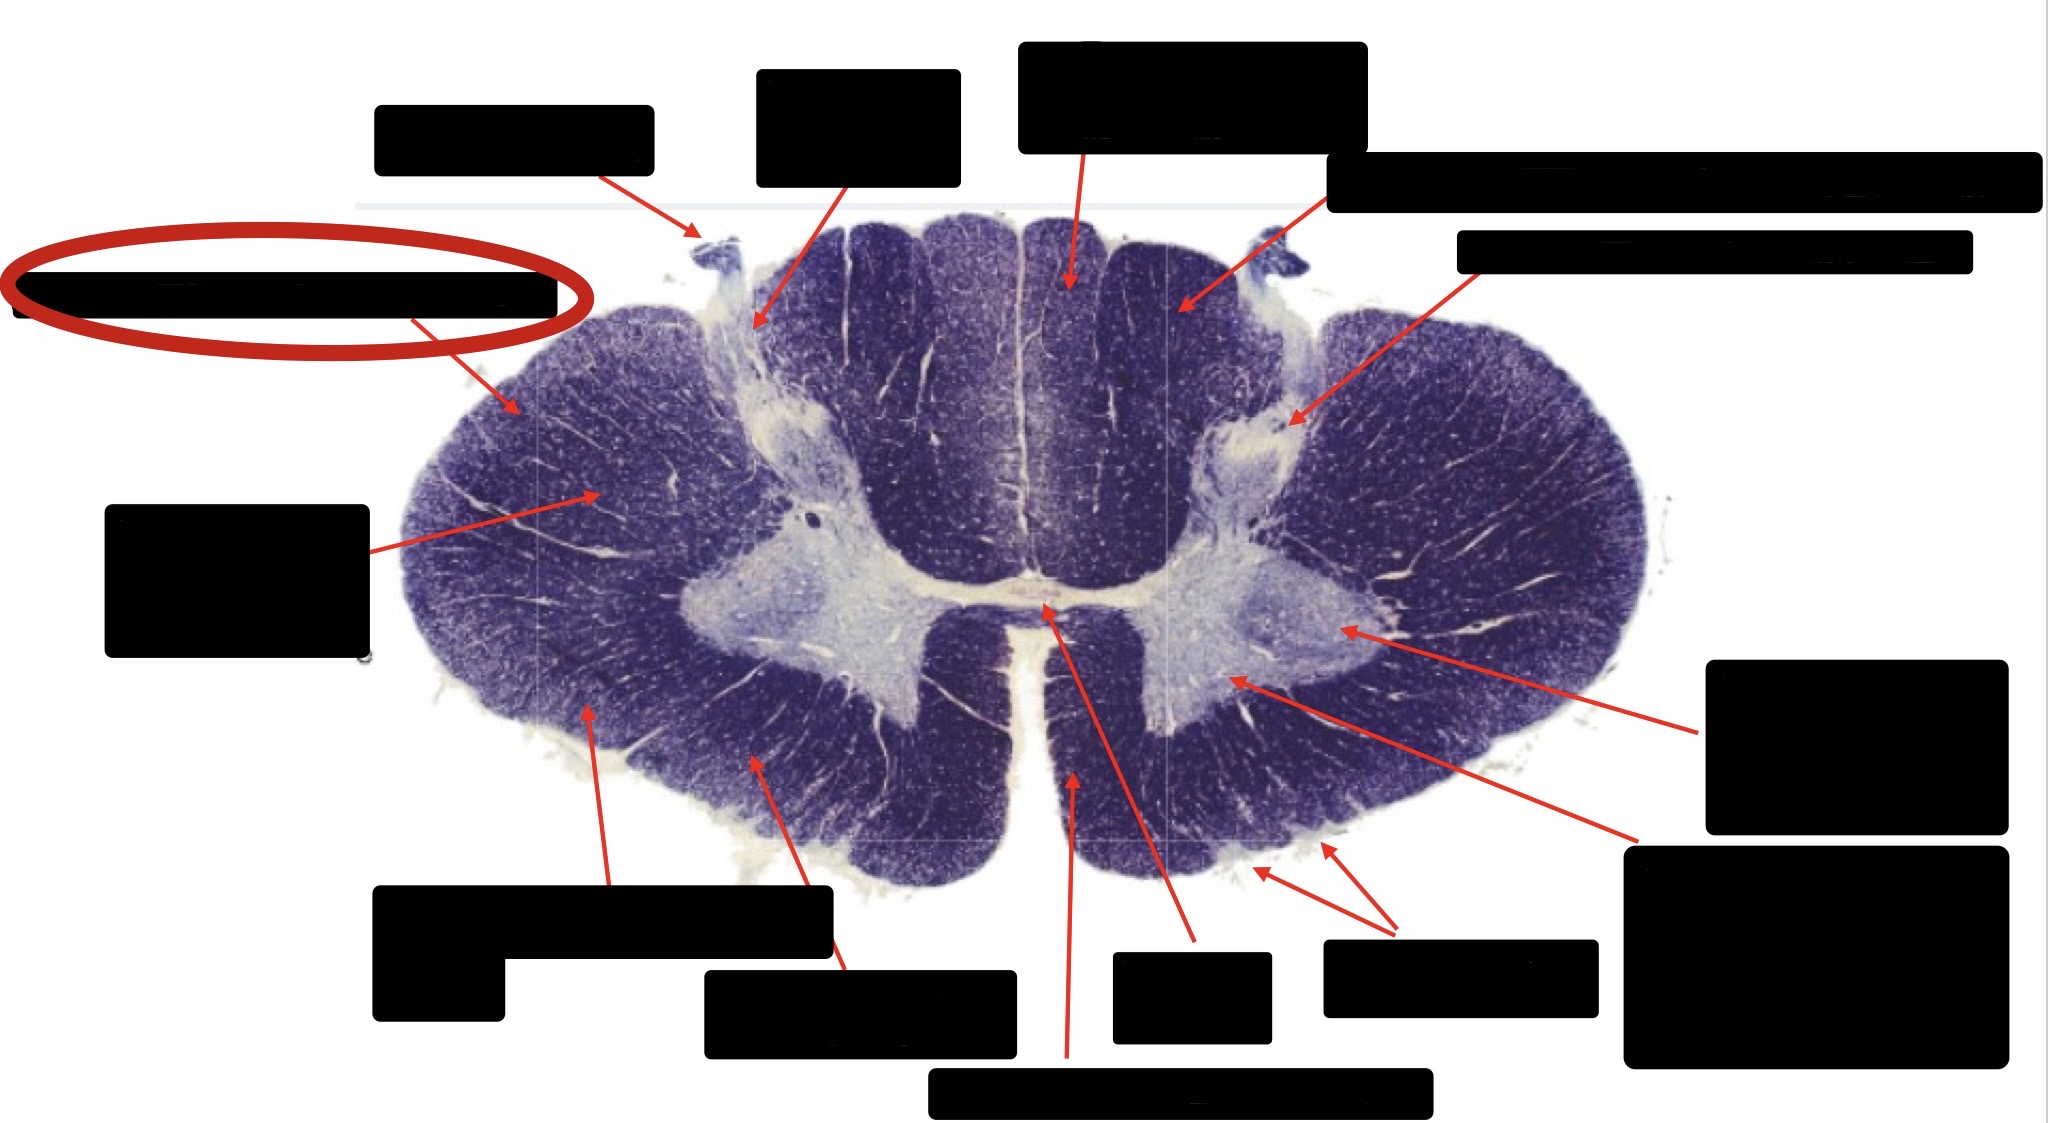

Central Canal

Posterior Column (Fasciculus Gracilis)

Large Fiber Entry Zone

Lissaeur’s Tract & Small Fiber Entry Zone

Substantia Gelatinosa

Lateral Corticospinal Tract

Ventral Root Fibers

Anterior Horn Motor Neurons

Anterior Medial Fissure

Dorsal Rootlet

Posterior Spinocerebellar Tract

Anterior Spinocerebellar Tract

Spinothalmic Tract

Posterior Column (Fasciculus Cuneatus)

Anterior Horn Motor Neurons (Distal Muscles)

Anterior Horn Motor Neurons (Proximal Muscles)

Anterior Corticospinal Tract